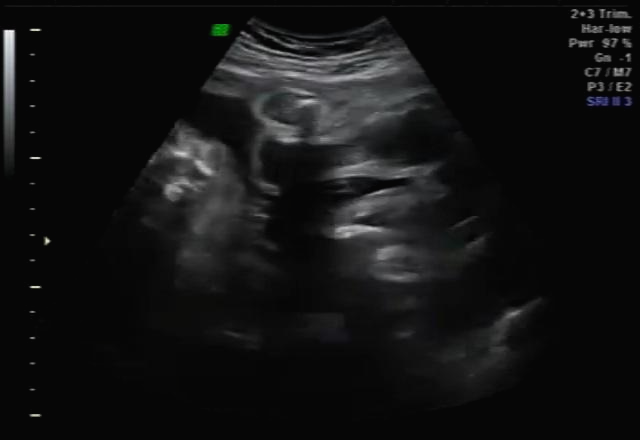

임신 20주 정밀 초음파 검사 : 성별 반전

20주 정밀초음파를 받았는데 아이 건강상태를 꼼꼼하게 확인하고 마지막으로 성별을 확인했는데 딸이라고... 저에게 성별 반전이 있었어요~ 그래서 믿을 수가 없어서 제가 초음파 검사를 했을 때마다 아들이라고 했는데 지금 딸이라 해서 너무 혼란스럽다고 하니 다시 누워보라며 다시 봐주셨는데 역시나 딸 ^^~ 확실한 성별 반전! 딸을 더 원했던 남편은 저의 기분을 생각하지 않고 너무 행복해하더라고요 ㅋㅋㅋㅋㅋ ;;